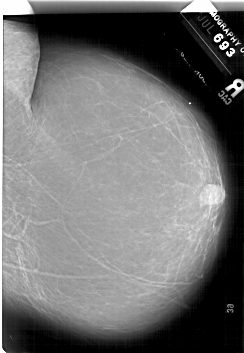

A_1882_1.RIGHT_CC

RIGHT_MLO LINES 6781 PIXELS_PER_LINE 4936 BITS_PER_PIXEL 12 RESOLUTION 43.5 NON_OVERLAY